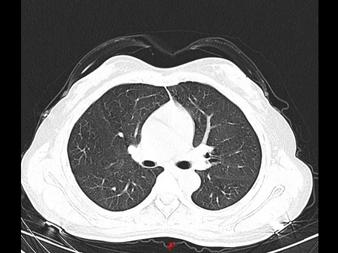

近日,郑州的张女士和王女士患了同一种“病”,她们感到头晕、乏力,遂到郑州市中心医院就诊。该院医生发现,两人的肺部CT均呈毛玻璃影,与新冠肺炎的表现基本上一模一样,然而二人并没有发烧及咳嗽、咳痰、呼吸困难等症状。

正当大家毫无头绪之时,该院呼吸与危重症医学科主任发现了端倪。原来,两位女士居家期间,因为害怕感染新冠肺炎,每天定时在家喷洒高浓度84消毒液,又没有开窗通风,从而引起过敏性肺泡炎。所幸,经过3天的抗过敏治疗后,二人复查胸部CT,影像基本恢复正常。

过敏性肺泡炎治疗前与治疗后CT影像